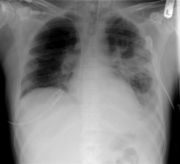

Příznaky zápalu plic jsou závislé na původci, který ho způsobuje a mohou se značně lišit.[1] Obecně se jako příznaky zápalu plic uvádí kašel, bolest na hrudi, horečka a obtížné dýchání. Diagnóza je stanovena na základě rentgenu plic a vyšetření sputa (tzv. chrchel, či hlen).[3] Léčba závisí na příčině zápalu plic, bakteriální infekce se léčí antibiotiky a podpůrnou symptomatologickou léčbou. Zápal plic je běžné onemocnění, které se postihuje všechny věkové skupiny a může být příčinou smrti u starších lidí[2][1] a lidí dlouhodobě nemocných. Proti některým typům zápalů plic existuje očkování jako například proti zápalu plic způsobené bakterií Streptococcus pneumoniae, či proti chřipkovým virům, kteří také mohou zápal plic vyvolat.[2] Prognóza onemocnění závisí na typu zápalu plic, na léčbě, komplikacích a na pacientově celkovém zdravotním stavu. Nejčastější formou zápalu plic bývá bronchopneumonie, kdy se zánět vyskytuje v oblasti průdušinek a okolních plicních tkáních. Zvláštním druhem zápalu plic je pak tuberkulóza.[2] Ohroženější skupinou obyvatelstva jsou kuřáci, lidi s oslabenou imunitou, či dlouhodobě nemocní pacienti.[3]

Nález při fyzikálním vyšetření plic může být normální, ale často ukazuje zhoršené rozpínání hrudníku na postižené straně. Při poslechu stetoskopem bývají nad postiženou oblastí slyšitelné přízvučné vlhké chrůpky a výjimečně se může objevit trubicové dýchání. Poklep nad postiženou plící může být ztemnělý, hrudní chvění (fremitus pectoralis) bývá zvýšené spíše než snížené, čímž se odlišuje od nálezu při pleurálním výpotku. Ačkoli jsou tyto příznaky významné, nejsou dostatečné ke stanovení diagnózy zápalu plic. Navíc studie prokázaly, že dva lékaři mohou určit rozdílné nálezy u stejného pacienta.[5][6] Pro diagnózu zápalu plic je rozhodujícím vyšetřením rentgenový snímek hrudníku.